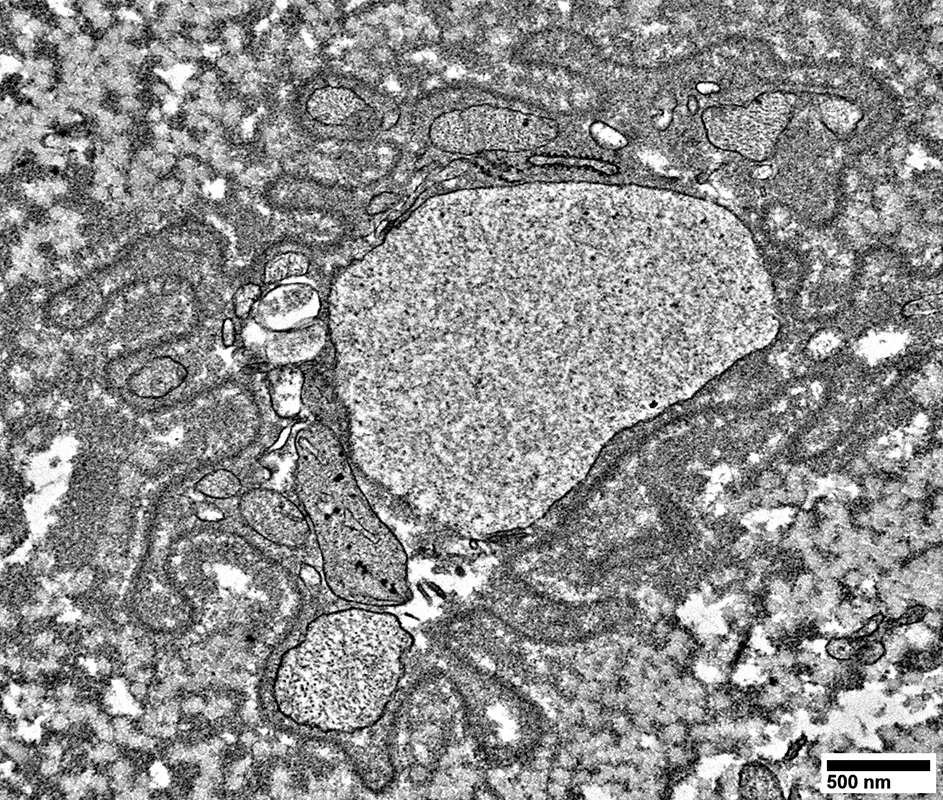

Axons surronded by layers of Schwann cell processes

Schwann cells around Axons: Contain Myelin Degradation Products

Myelin Pathology: Early